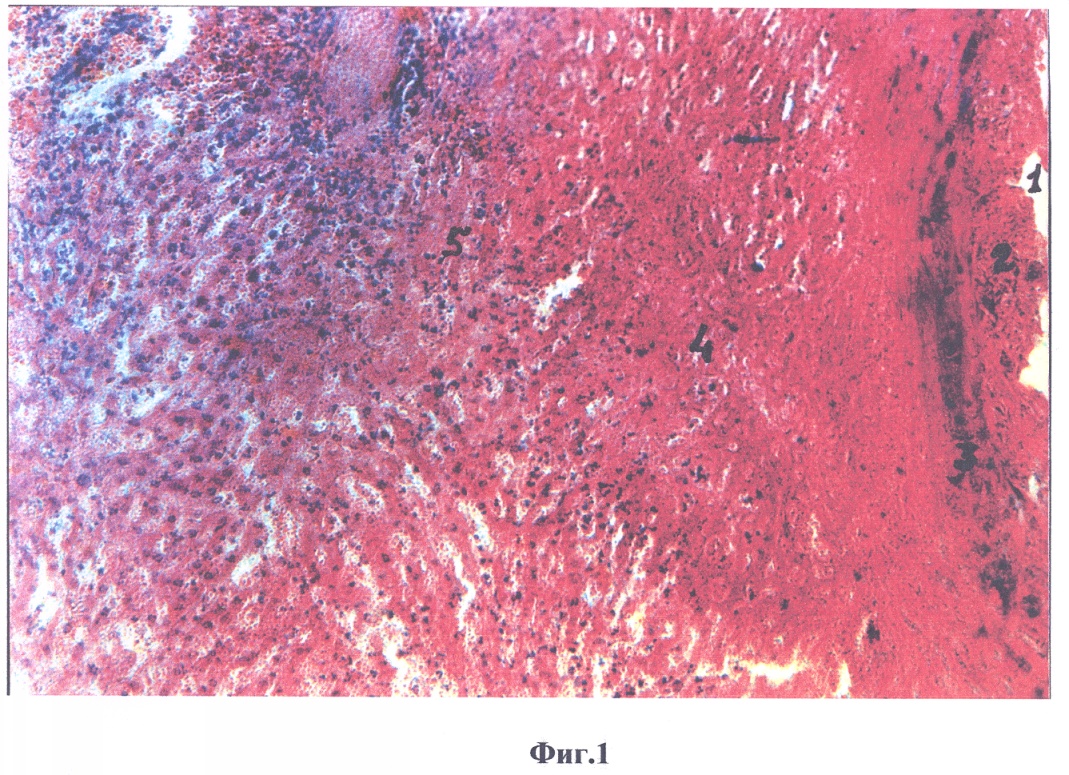

На фиг.1 изображено, что в зоне введения этанола через 24 часа отмечается массовый некроз гепатоцитов и всех клеточных элементов соединительной ткани. Зона некроза ограничена лейкоцитарным валом. За лейкоцитарным валом располагается перинекротическая зона, где наряду с морфологически нормальными гепатоцитами имеется значительное количество гепатоцитов, подвергшихся отсроченной гибели и дегенеративно измененные гепатоциты. В перинекротической зоне также отмечается гиперемия сосудов, диапедез эритроцитов и диффузная инфильтрация тканей печени лейкоцитами.